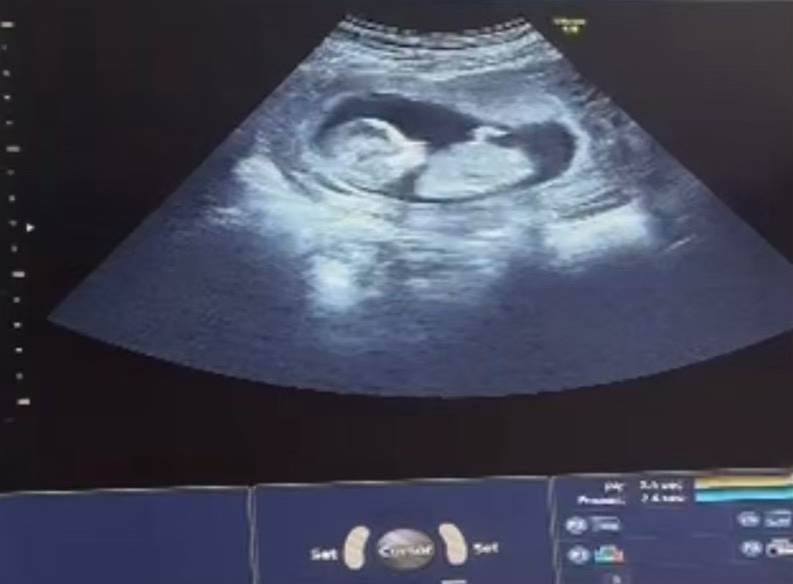

埼玉県に住む黒木さん夫妻は、子宮がんにより子宮を摘出した妻・優美さんの妊娠不可能な診断を受け、国内での不妊治療が不可能となってから海外での代理出産を決断しました。夫妻はジョージアで代理母を見つけ、国内で保存されていた受精卵を移送しましたが、受精卵の適合性や高額な費用、そして法的手続きに苦労しました。国内では代理出産を禁止する内容を含む法律案が話題となり、夫妻は自分たちの選択が否定されるような社会的な矛盾を感じていました。それでも、夫妻はエコー動画を見守りながら出産予定日の5月を待ち望んでいます。